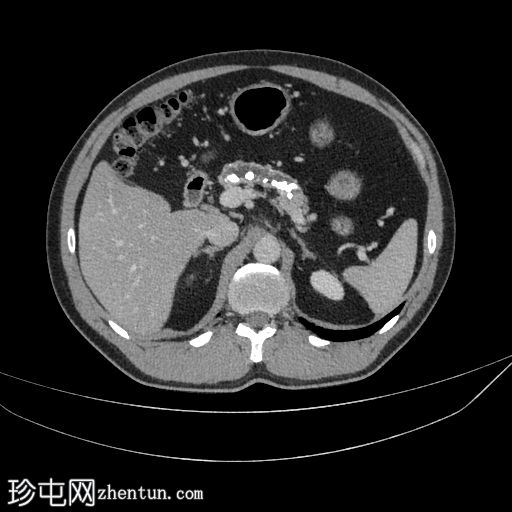

CT

轴位

平扫

胰腺萎缩、粗大钙化及主胰管扩张

无急性胰腺炎征象

肝脂肪变性

左侧结肠憩室

主胰管扩张、胰腺萎缩和钙化是慢性胰腺炎诊断的关键。该患者有反复发作的急性胰腺炎病史。